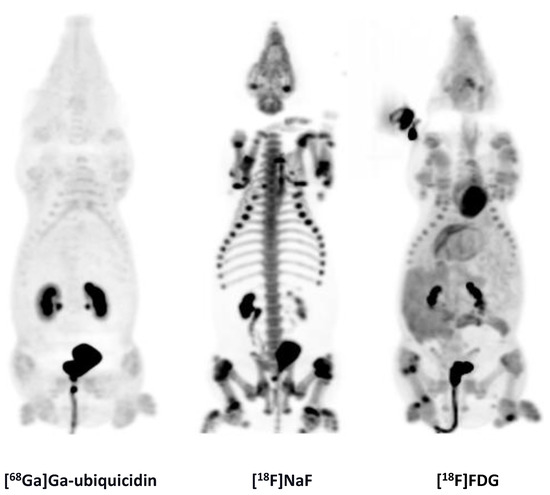

While previous evaluation in murine subcutaneous S. aureus infections showed uptake of [68Ga]Ga-DOTA-K-A9 [9,14], we saw no increased tracer activity of the two S. aureus phage displayed selected peptides, [68Ga]Ga-DOTA-K-A9 (Figure 1) and [68Ga]Ga-GSG-KA-11 (Figure 2) in 9 and 5, respectively, porcine OM lesions. Figure 3 shows the bio-distribution of the peptides in pigs. Both peptides were excreted by the liver and kidneys.

[18F]FDG (left) and Ga-DOTA-K-A9 (right) accumulation is shown in an OM lesion in the right calcaneus and distal II metatarsus of pig 4 (indicated by arrows). The lesions show sequester formation and lysis of the cortical bone on CT in the axial view (middle). Comparable SUV scales are shown to the right of the PET images.

MIPs of the [68Ga]Ga-ubiquicidin, [18F]NaF, and [18F]FDG distribution in pig 9.